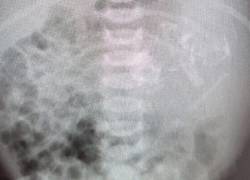

Una bebé nació con el feto de su hermano gemelo en su estómago La condición se conoce como ‘fetus in fetu’ y solo ocurre una vez de cada 500 mil nacimientos. Internacional 30/07/2021 - 12:58